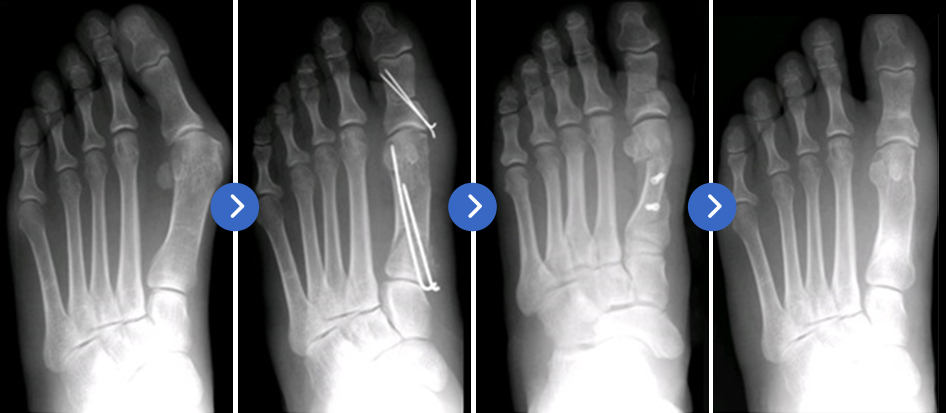

무지외반증은 발을 직접 보기만 하여도 변형된 형태를 알 수 있음으로 진단하기는 아주 쉽습니다.

그러나, 방사선 찰영과 의사의 진찰 소견을 종합하여, 실제 발가락과 관절의 형태를 정확하게 파악하여야 치료 방침이 결정됨으로

필요시에는 병원을 찾아야 합니다.

수술의 여부는 환자의 불편함 정도와 의학적 소견을 종합하여 결정하는 것이지만 가장 중요한 것은 환자가 주관적으로 느끼는 불편함의 정도이며 아무리 변형이 심하다고 해도 그것만으로 수술 여부를 결정하는 것은 아닙니다. 미용적인 측면과 단지 예쁜 구두를 신고 싶어서 수술 받기를 원하는 경우도 있는데 이러한 경우에는 수술 부위에 흉터가 남으며 수술 후에도 하이힐 등의 불편한 신발은 이후에도 증상의 재발 이나 통증이 생길 수 있음을 알고 있어야 합니다. 수술적 치료방법에는 매우 다양한 수술법이 있고 각각의 장단점이 있습니다. 환자의 나이, 변형의 심한 정도, 환자가 가장 불편하게 생각하는 부분 등을 고려하여 수술 방법을 결정하게 됩니다. 수술법은 일반적으로는 돌출 부위의 뼈를 깎아내고 외반된 중족골과 족지골을 잘라서 각을 교정하며 금속핀이나 나사못을 이용하여 고정하는 수술을 합니다. 외측 연부조직을 늘여주는 술기도 포함됩니다.